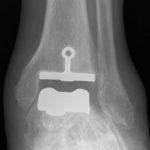

Prothèses de cheville

Le développement récent des prothèses de cheville a abouti à une solution fiable et innovante dans le traitement de l’usure articulaire de la cheville. Elles sont à présent une alternative sérieuse à l’arthrodèse.